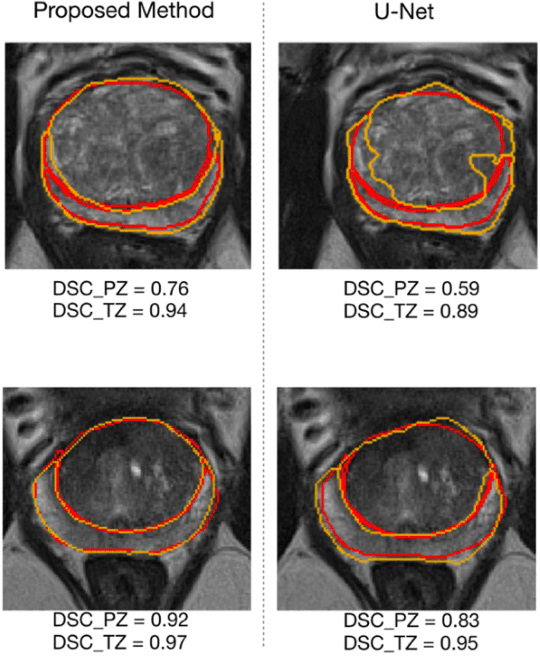

Abstract:Prostate cancer is the second leading cause of cancer death among men in the United States. The diagnosis of prostate MRI often relies on the accurate prostate zonal segmentation. However, state-of-the-art automatic segmentation methods often fail to produce well-contained volumetric segmentation of the prostate zones since certain slices of prostate MRI, such as base and apex slices, are harder to segment than other slices. This difficulty can be overcome by accounting for the cross-slice relationship of adjacent slices, but current methods do not fully learn and exploit such relationships. In this paper, we propose a novel cross-slice attention mechanism, which we use in a Transformer module to systematically learn the cross-slice relationship at different scales. The module can be utilized in any existing learning-based segmentation framework with skip connections. Experiments show that our cross-slice attention is able to capture the cross-slice information in prostate zonal segmentation and improve the performance of current state-of-the-art methods. Our method significantly improves segmentation accuracy in the peripheral zone, such that the segmentation results are consistent across all the prostate slices (apex, mid-gland, and base).

Abstract:Our main objective is to develop a novel deep learning-based algorithm for automatic segmentation of prostate zone and to evaluate the proposed algorithm on an additional independent testing data in comparison with inter-reader consistency between two experts. With IRB approval and HIPAA compliance, we designed a novel convolutional neural network (CNN) for automatic segmentation of the prostatic transition zone (TZ) and peripheral zone (PZ) on T2-weighted (T2w) MRI. The total study cohort included 359 patients from two sources; 313 from a deidentified publicly available dataset (SPIE-AAPM-NCI PROSTATEX challenge) and 46 from a large U.S. tertiary referral center with 3T MRI (external testing dataset (ETD)). The TZ and PZ contours were manually annotated by research fellows, supervised by genitourinary (GU) radiologists. The model was developed using 250 patients and tested internally using the remaining 63 patients from the PROSTATEX (internal testing dataset (ITD)) and tested again (n=46) externally using the ETD. The Dice Similarity Coefficient (DSC) was used to evaluate the segmentation performance. DSCs for PZ and TZ were 0.74 and 0.86 in the ITD respectively. In the ETD, DSCs for PZ and TZ were 0.74 and 0.792, respectively. The inter-reader consistency (Expert 2 vs. Expert 1) were 0.71 (PZ) and 0.75 (TZ). This novel DL algorithm enabled automatic segmentation of PZ and TZ with high accuracy on both ITD and ETD without a performance difference for PZ and less than 10% TZ difference. In the ETD, the proposed method can be comparable to experts in the segmentation of prostate zones.